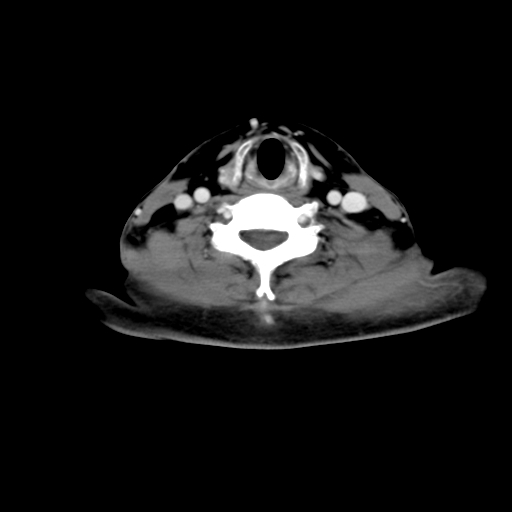

标题: CT24019:男,45岁,发现颈部肿物5个月。 [打印本页]

标题: CT24019:男,45岁,发现颈部肿物5个月。

男,45岁,发现颈部肿物5个月,彩超示:双侧颈部及下颌部软组织增厚。

考虑双侧颈项部良性对称性脂肪增多症。

双侧颈项部脂肪沉积

双侧颈项部脂肪沉积。